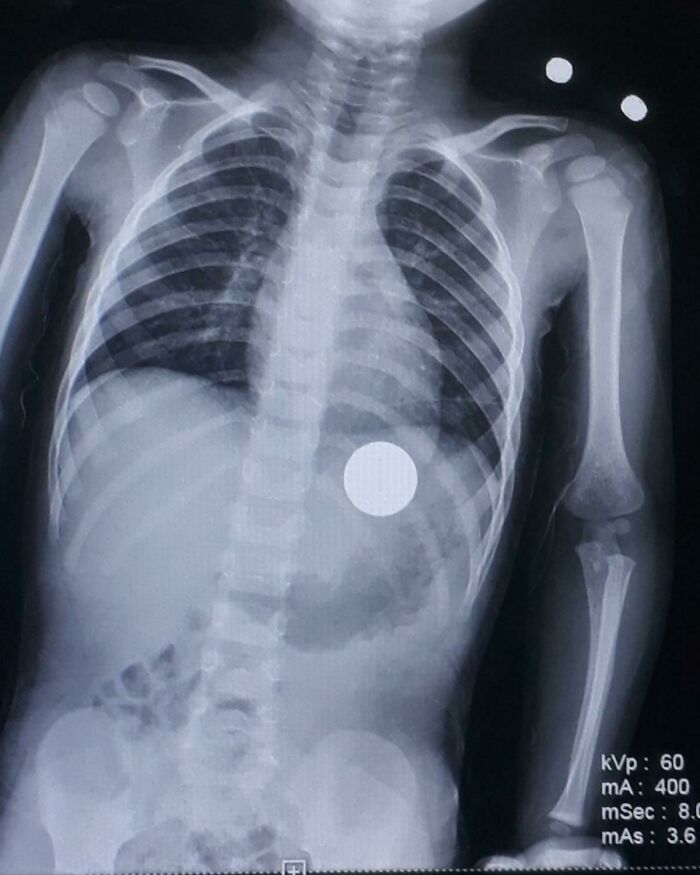

lilpastababy:

A kid came in for a cough at the urgent care I work at and they did a chest X-ray and discovered that he had this. Everyone was freaking out lol